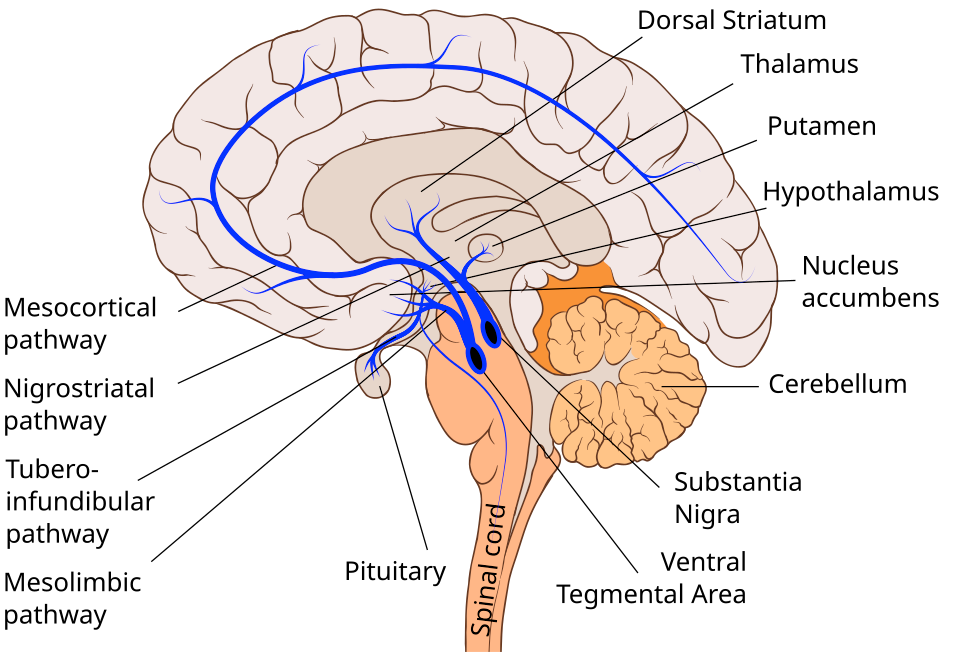

Сразу хочу пояснить: СДВГ — это не «привычка к клиповому мышлению» и не «лень». В основе ле��ит нарушение дофаминовой системы мозга. Дофамин — это нейромедиатор, который отвечает за мотивацию, ощущение вознаграждения и способность удерживать внимание на задаче. При СДВГ его банально не хватает.

Это не метафора. Исследование 2009 года с позитронно-эмиссионной томографией (почти 100 участников) показало, что в ключевых зонах системы вознаграждения мозга у людей с СДВГ значимо снижена активность дофаминовых рецепторов [1]. Те же авторы потом показали, что этот дефицит напрямую связан с проблемами мотивации, причём только у группы с СДВГ, у контрольной группы такой связи не было [2].

Ещё в 2001 году группа нейроучёных провела ПЭТ-исследование и обнаружила, что интенсивное удовольствие от музыки, те самые «мурашки», сопровождается всплеском активности в зонах вознаграждения мозга. Тех же самых, которые реагируют на еду, секс и другие базовые награды. Эта работа набрала больше 4000 цитирований и стала отправной точкой для целого направления [7]. Десять лет спустя, в 2011 году, с помощью более точного ПЭТ-сканирования впервые показали, что при прослушивании музыки в мозге реально выделяется дофамин [8]. Музыка это единственный абстрактный стимул, который запускает ту же нейрохимическую реакцию, что и базовые потребности.